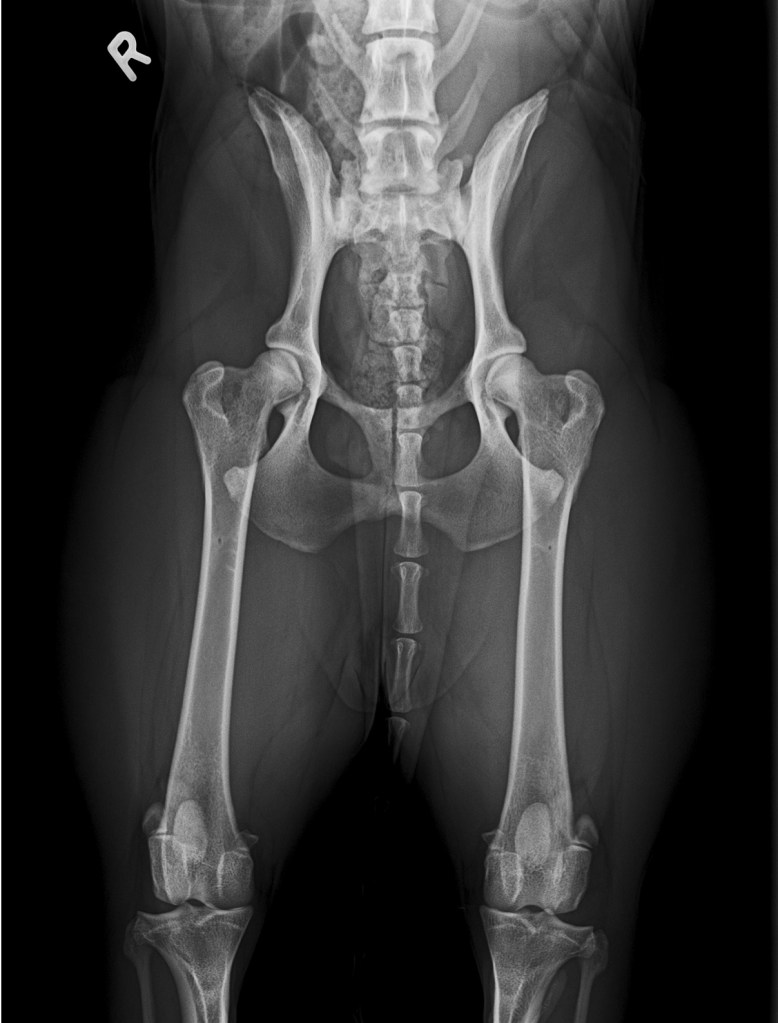

Röntgenergebnisse

HD: A/A ED: frei OCD Schulter: frei LS-ÜGW: 0 (frei)